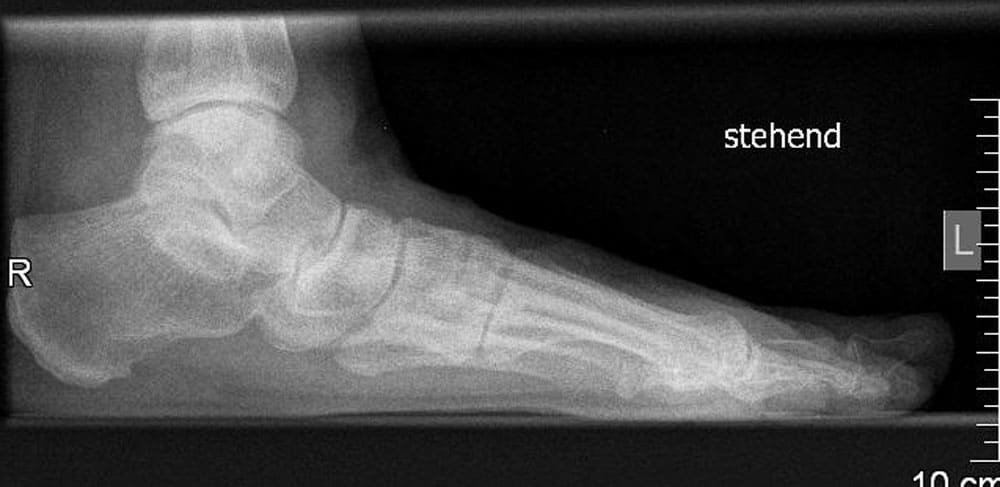

Eine Röntgen-Untersuchung des Fußes unter Belastung (im Stehen) gibt weitere wichtige Informationen zur Wahl der Operationsmethode. Eine gleichzeitige Großzehengrundgelenksarthrose ändert z.B. vollständig die Vorgehensweise. Verschiedene Winkel werden auf dem Röntgenbild gemessen, um das Ausmaß der Fehlstellung festzustellen. Dementsprechend können dann die operativen (invasiven) Techniken z.B. für einen schweren Hallux valgus angepasst werden. Das Vorhandensein eines Knick-Senkfußes muss auch in die operative Strategie mit einbezogen werden, dieser macht eine Korrektur notwendig.

Die seitliche Röntgen-Aufnahme bildet eine Knick-Senkfuß-Fehlstellung ab. Dieses ist eine wichtige Information zur operativen Vorgehensweise.